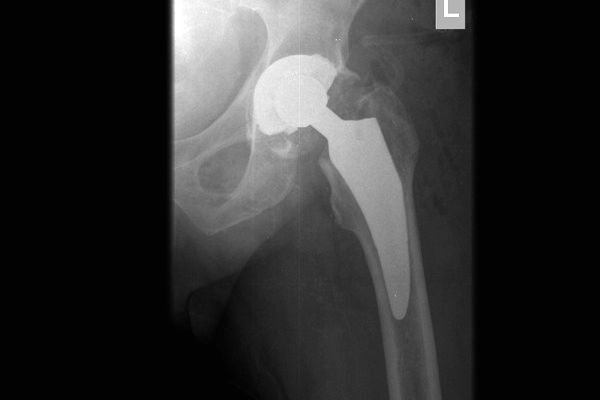

Gabinet ortopedyczny prowadzony przeze mnie specjalizuje się w leczeniu schorzeń i urazów kończyn górnych i dolnych. Zajmuję się leczeniem choroby zwyrodnieniowej stawu biodrowego i kolanowego, uszkodzeń wewnętrznych stawu kolanowego i barkowego, złamań w obrębie kończyn górnych i dolnych oraz urazów ścięgien i mięśni kończyn górnych i dolnych. Ponadto wykonuję diagnostykę USG narządu ruchu i badanie preluksacyjne (USG bioderek niemowląt). Leczę również neuropatie uciskowe kończyn (zespół kanału nadgarstka, rowka nerwu łokciowego, kanału Guyona) oraz uszkodzenia wewnętrzne stawów kończyn górnych i dolnych. Zapraszam do mojego gabinetu, gdzie dobiorę odpowiednie do schorzenia metody leczenia i zakwalifikuję do ewentualnego leczenia operacyjnego. W celu umówienia się na wizytę proszę o kontakt telefoniczny z rejestracją gabinetu ortopedycznego w Lesznie.